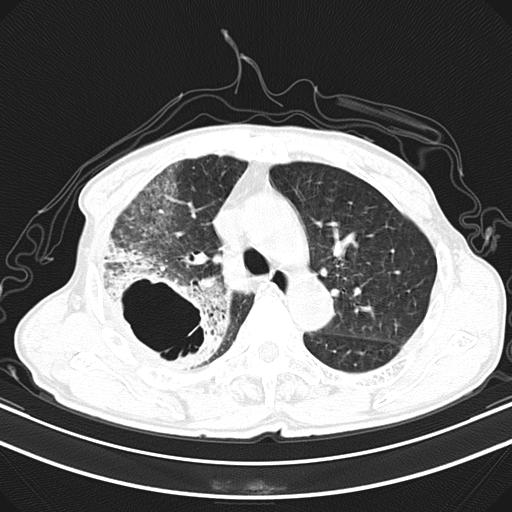

抗炎治疗10天后复查

抗炎治疗10天后复查:右上肺模糊阴影明显减少。